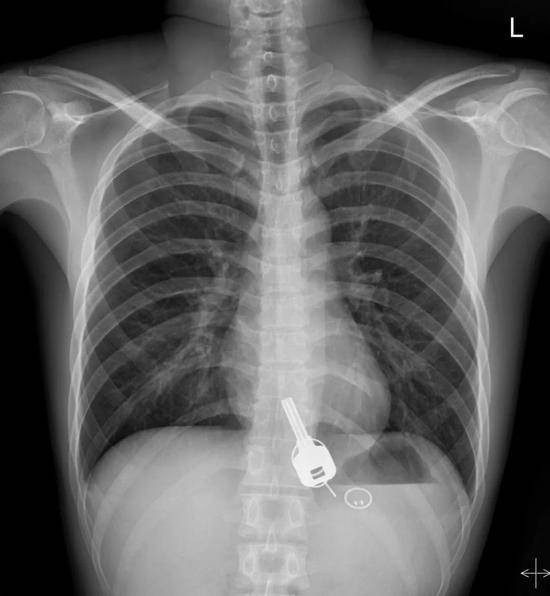

Hình ảnh X-quang cho thấy chìa khóa nằm gọn trong dạ dày của anh Thường.

Gần đây, một người đàn ông 26 tuổi họ Thường sống ở Đông Quan, Quảng Tây vừa trải qua một tai nạn hy hữu sau một cơn say.

Được biết, anh Thường sau khi uống rượu say đã về nhà vào nửa đêm và phát hiện bị mất chìa khóa xe và thẻ từ vào nhà. Sáng hôm sau, khi tỉnh dậy, anh Thường cảm thấy bị đau ở ngực và cơn đau đó tăng thêm từng giờ. Cuối cùng, anh đã được người nhà đưa vào bệnh viện để cấp cứu.

Kết quả kiểm tra cho thấy, nguyên nhân khiến anh Thường bị đau vì phát hiện trong dạ dày có 1 chìa khóa, 2 vòng sắt và 1 thẻ từ. Cuối cùng, thông qua nội soi dạ dày không đau, bác sĩ đã giúp anh Thường lấy những vật đó ra thành công.

Theo báo Tân Hoa Xã, anh Thường nói rằng không nhớ làm sao mình có thể nuốt được chìa khóa vào trong bụng. Tối hôm đó, anh trở về nhà không tìm thấy chìa khóa và nghĩ rằng chắc là bị rơi ở dọc đường, không hề quan tâm đến trường hợp khác và không bao giờ nghĩ rằng nó đang ở trong bụng mình.

Về việc làm sao lấy được vật dụng bằng kim loại kia ra khỏi bụng của anh Thường, bác sĩ Trương Dung Vũ, làm việc ở khoa tiêu hóa bệnh viện Nhân dân Đông Quan cho biết, lúc đầu bác sĩ xem xét và nhận thấy sẽ gặp một ít khó khăn khi lấy chìa khóa ra. Bởi vì chìa khóa không có góc nhọn và sẽ không gây thiệt hại cho đường tiêu hóa quá lớn. Tuy nhiên, nhưng khi nội soi kỹ càng hơn thì phát hiện chìa khóa bị mắc kẹt ở lối vào của thực quản gần cổ họng. Nếu như bị buộc phải lấy ra thì thực quản sẽ bị rách.

Bác sĩ Trương cho biết, nếu như không thể loại bỏ nó dưới ống soi dạ dày thì chỉ còn 2 cách. Một là để bệnh nhân tự lấy bằng đường bài tiết, nhưng do chìa khóa quá lớn và khả năng từ khoang dạ dày đến ruột quá nhỏ sẽ dẫn đến việc gây tắc nghẽn đường ruột. Hai là phải thực hiện phẫu thuật mở. May mắn thay, bác sĩ đã nhanh chóng nghĩ ra một phương pháp khác là đưa ống soi dạ dày không đau vào người. Dưới sự gây mê, các cơ ở lối vào thực quản giãn ra và cuối cùng chìa khóa đã được lấy một cách an toàn.

Hiện tại, tình hình sức khỏe của người đàn ông đang dần phục hồi. Nhưng tai nạn hy hữu này khiến nhiều người không khỏi bất ngờ và cảnh báo mọi người nên cẩn thận khi say rượu để tránh gặp phải tình trạng tương tự.